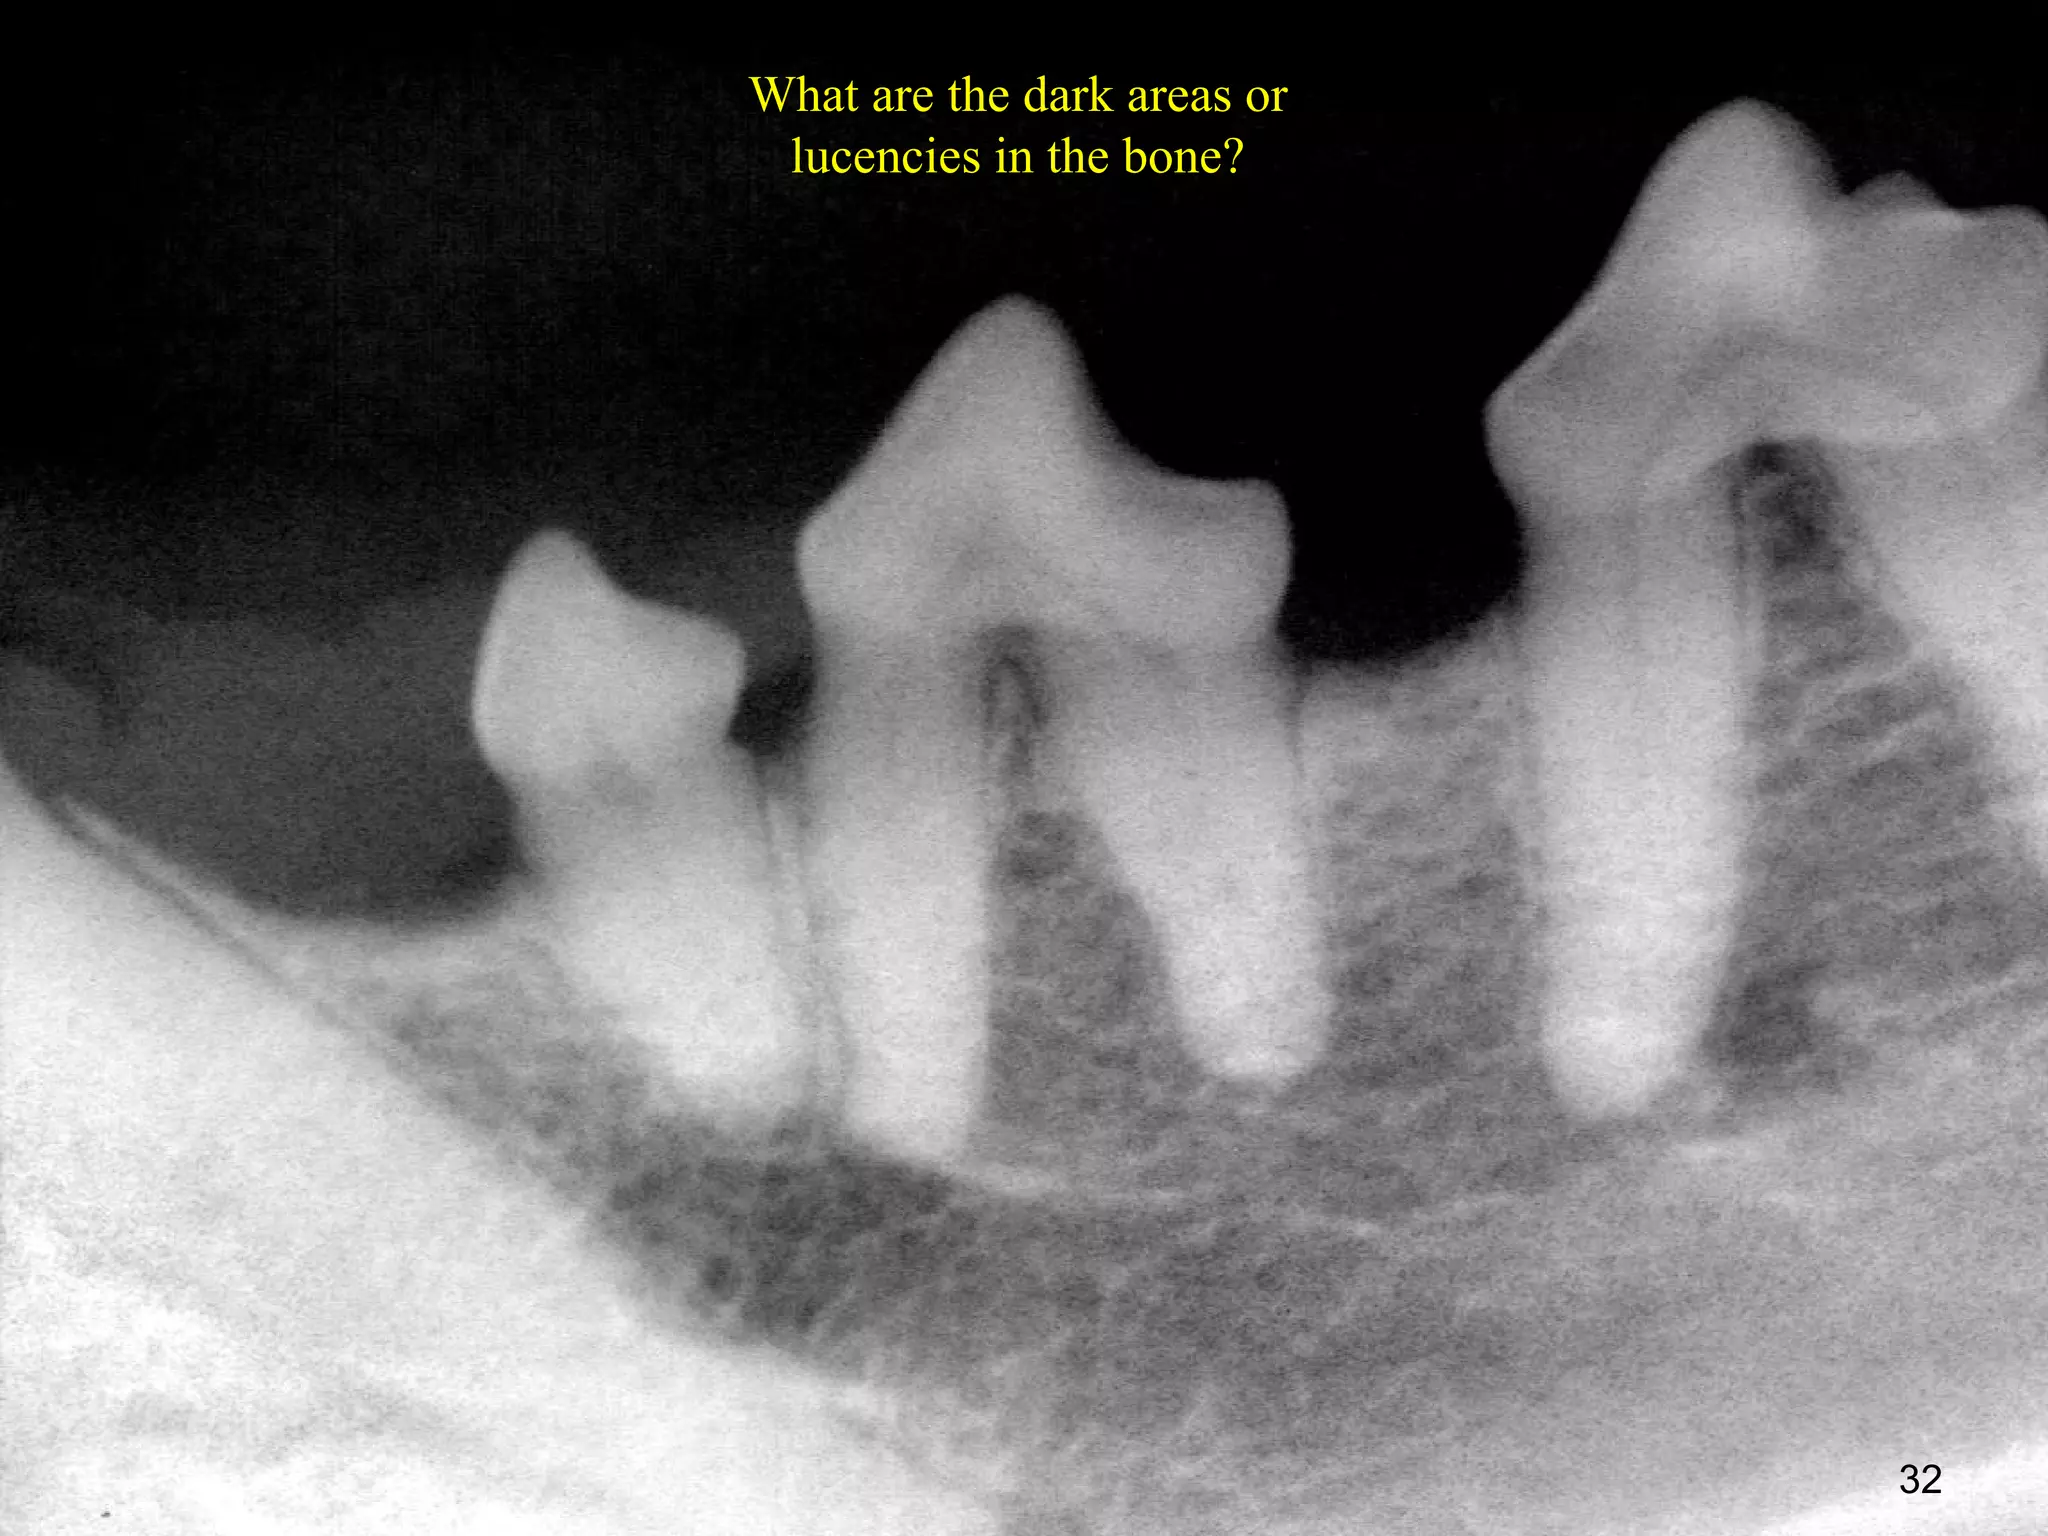

What are the dark areas or

lucencies in the bone?

32

• 32.

What are thedark areas or lucencies in the bone? 32